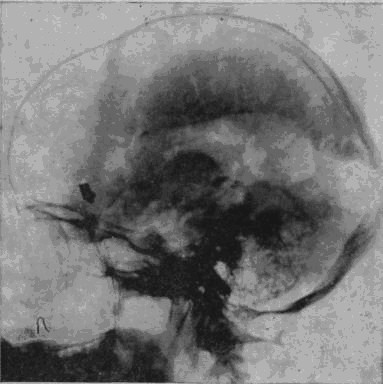

«Младший лейтенант Засецкий, 23 лет, получил 2 марта 1943 года пулевое проникающее ранение черепа левой теменно-затылочной области. Ранение сопровождалось длительной потерей сознания и, несмотря на своевременную обработку раны в условиях полевого госпиталя, осложнилось воспалительным процессом, вызвавшим слипчивый процесс в оболочках мозга и выраженные изменения в окружающих тканях мозгового вещества».

Осколок внедрился в вещество задних, теменно-затылочных отделов мозга и разрушил мозговую ткань этой области.

Рис. 16. Черное пятно в правом полушарии – осколок, расположенный под кожей от поверхностного шрапнельного ранения, полученного им за год до основного ранения